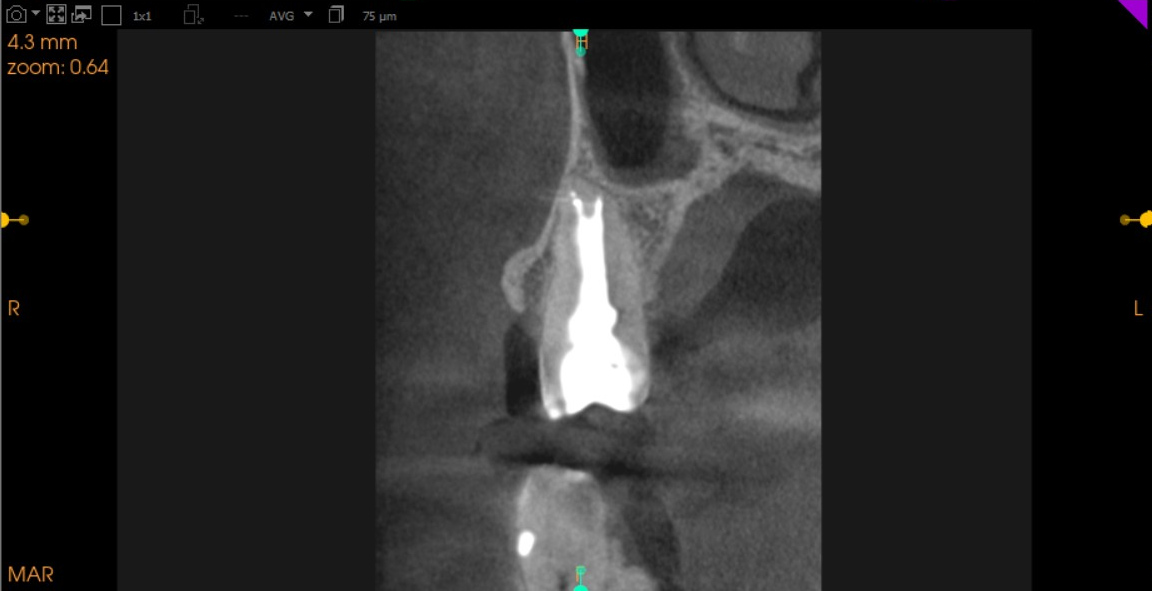

Post-Op Root Canal